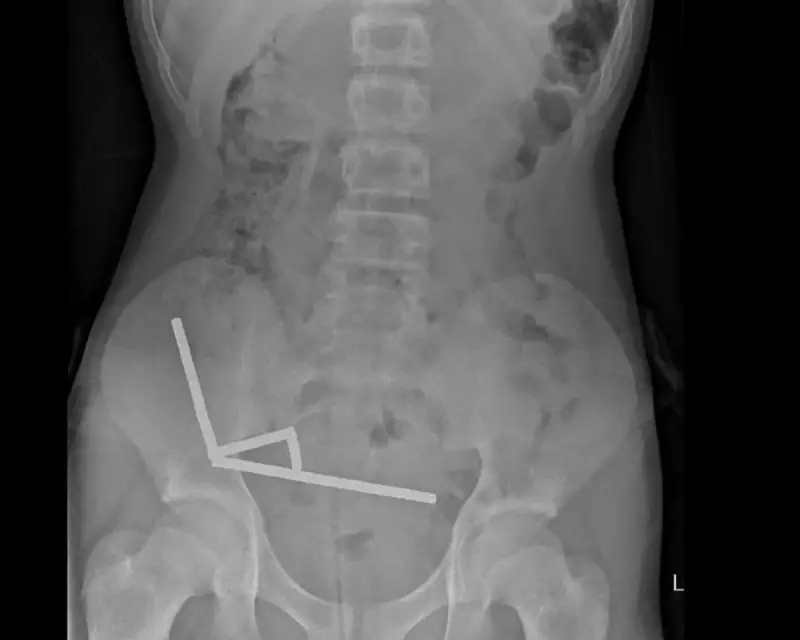

In a chilling medical emergency that highlights the hidden dangers of online shopping, surgeons in New Zealand have successfully removed multiple high-powered magnets from a teenager's intestines after they caused severe internal damage.

The case, reported by Wellington Hospital surgeons, involved a teen who had swallowed several rare-earth magnets purchased from the popular discount shopping platform Temu. These tiny but incredibly strong magnets, often marketed as "Buckyballs" or neodymium magnets, can create devastating internal injuries when multiple pieces are swallowed.

"When these powerful magnets separate inside the digestive system and then reconnect through intestinal walls, they essentially create a vice-like grip that cuts off blood supply," explained one medical professional familiar with the case.